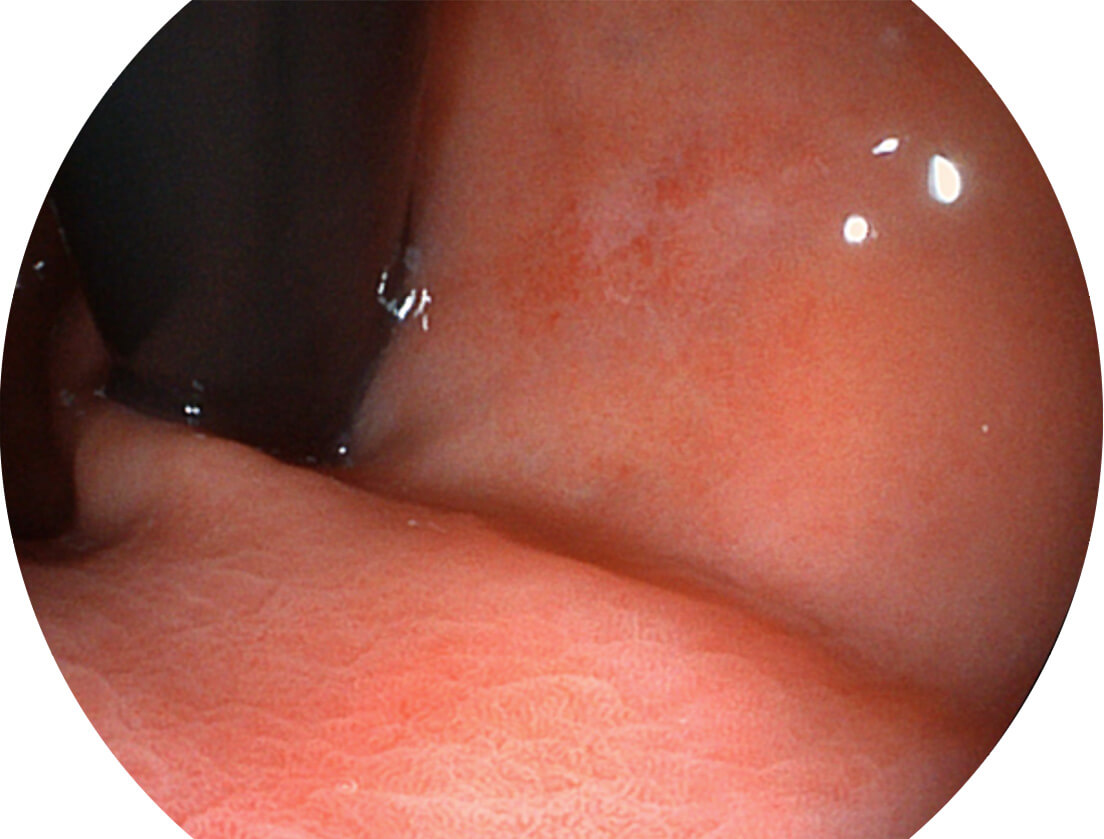

白光图像

VIST图像